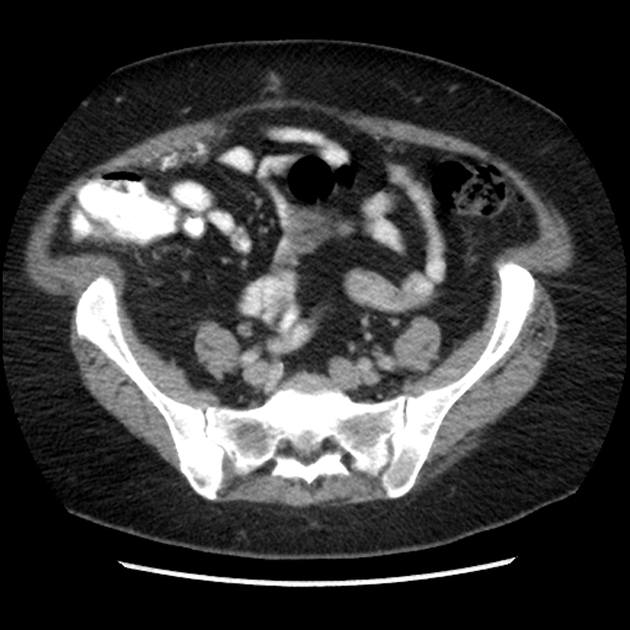

Di căn phúc mạc

Di căn phúc mạc - Ảnh 2

» Thông tin: Nữ giới – 60 tuổi.

» Lâm sàng: Đau mạn sườn phải / Tiền sử buồng trứng.